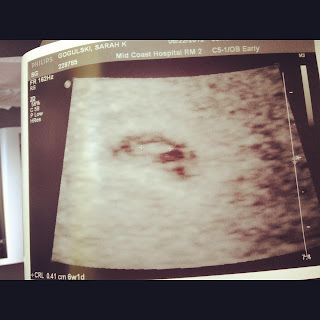

I had my first ultrasound at 6 weeks and 1 day, and baby was measuring exactly with my estimated due date. As you can see, the ultrasound just looked like a tiny peanut! I couldn't believe that was what my little baby looked like at 6 weeks!

My first Ultrasound 6 weeks 1 day